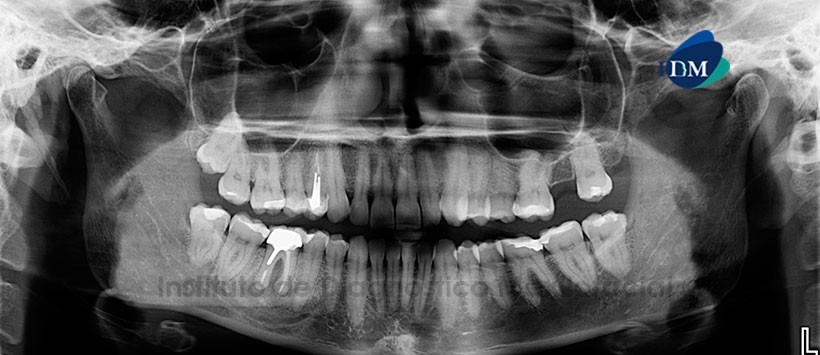

Paciente femenino, 49 años de edad, es referido al Instituto de Diagnostico Maxilofacial (IDM) para evaluación pos tratamiento de conductos en pieza 4.6.

A la evaluación de la radiografía panorámica, se aprecia aplanamiento del contorno de los cóndilos mandibulares, neumatización alveolar de los senos maxilares con presencia de antrolito en el seno maxilar izquierdo. En la pieza 4.6 se observa corona protésica, espigo intrarradicular y material de obturación de conductos con proceso osteolítico periapical. (Figura 1).